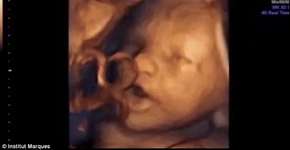

Foto: (© Institut Marques)

Vídeo mostra feto ‘cantando’ dentro da barriga de mãe